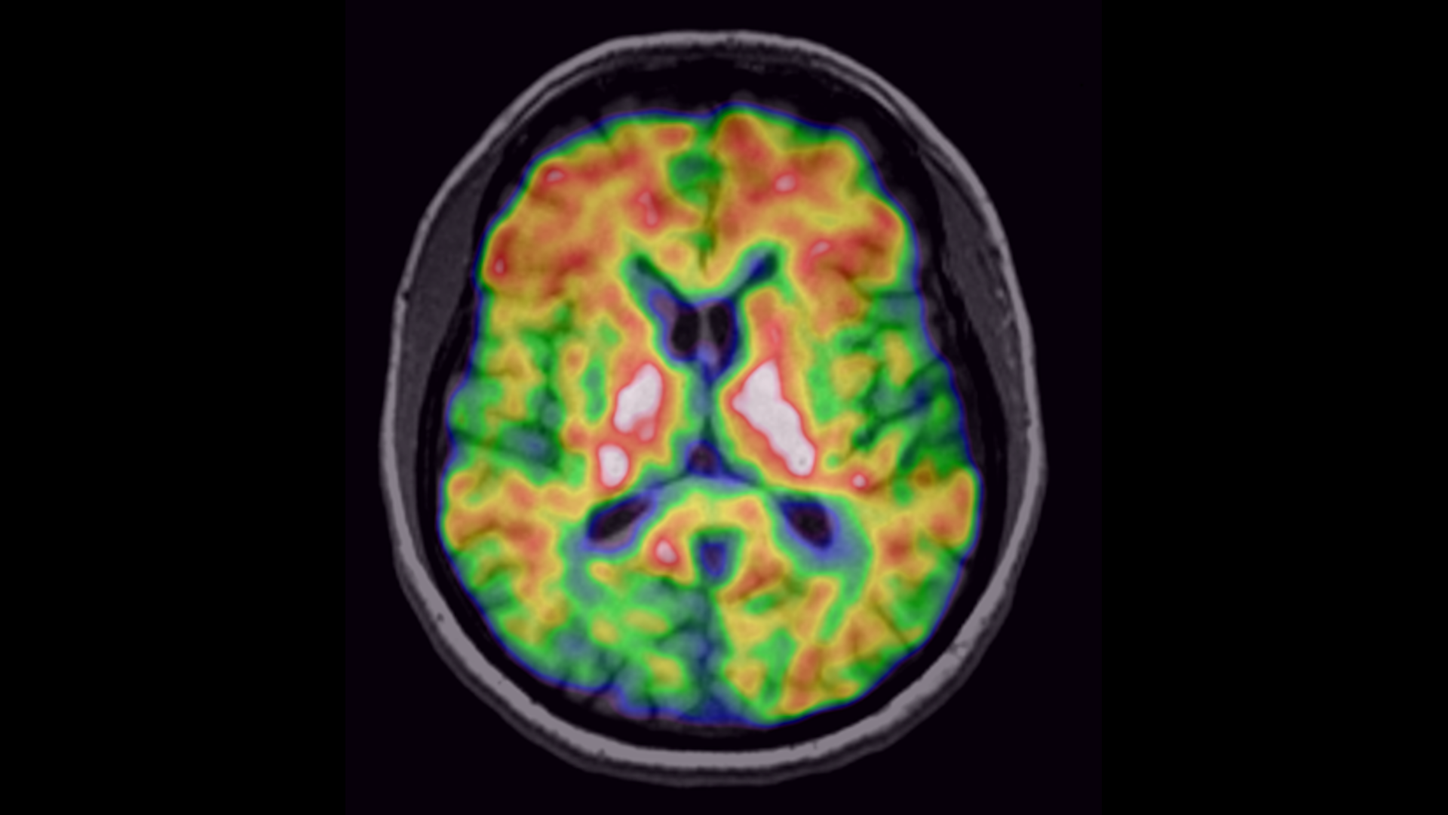

NeurologyDiscover our solutions for imaging and image guided therapy in Neurology

Neurological disorders can threaten the fundamental hope of a happy and independent life, spent with the people we care about. Helping patients achieve their highest potential independence by supporting your diagnosis and treatment is what we strive for.